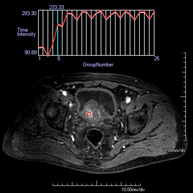

Prueba diagnóstica no invasiva que consiste en la obtención de imágenes de alta definición anatómica del sistema urinario mediante el empleo de un campo electromagnético y ondas de radio (con un emisor y un receptor). No utiliza radiación ionizante. Requiere el uso de contraste paramagnético (Gadolinio) que se excretará por el sistema urinario y nos permitirá obtener imágenes en 2D y 3D. - RM Próstata

Prueba diagnóstica no invasiva que consiste en la obtención de imágenes de alta definición anatómica de la glándula prostática mediante el empleo de un campo electromagnético y ondas de radio (con un emisor y un receptor). No utiliza radiación ionizante. Se utiliza una bobina endorrectal para obtener imágenes de máxima definición anatómica de la próstata, que permitirá realizar el estudio espectroscópico (estudio a nivel molecular que ayuda a diferenciar las células de origen maligno o tumoral). También se realiza el estudio con contraste paramagnético que aporta una mejor definición tisular. Esta prueba dura unos 40 minutos, durante los cuales el paciente deberá estar lo más quieto posible. Como preparación previa requiere limpieza del colon. Esta prueba está especialmente indicada en aquellos pacientes con sospecha de neoplasia de próstata, con neoplasia de próstata conocida para el estadiaje tumoral, estudio de localización del tumor prostático como guía o mapa para la biopsia, seguimiento de los pacientes con neoplasia de próstata tratados con tratamiento quirúrgico o radioterápico, sospecha de recidiva de la neoplasia de próstata, etc. - RM Cuerpo entero (Total body)